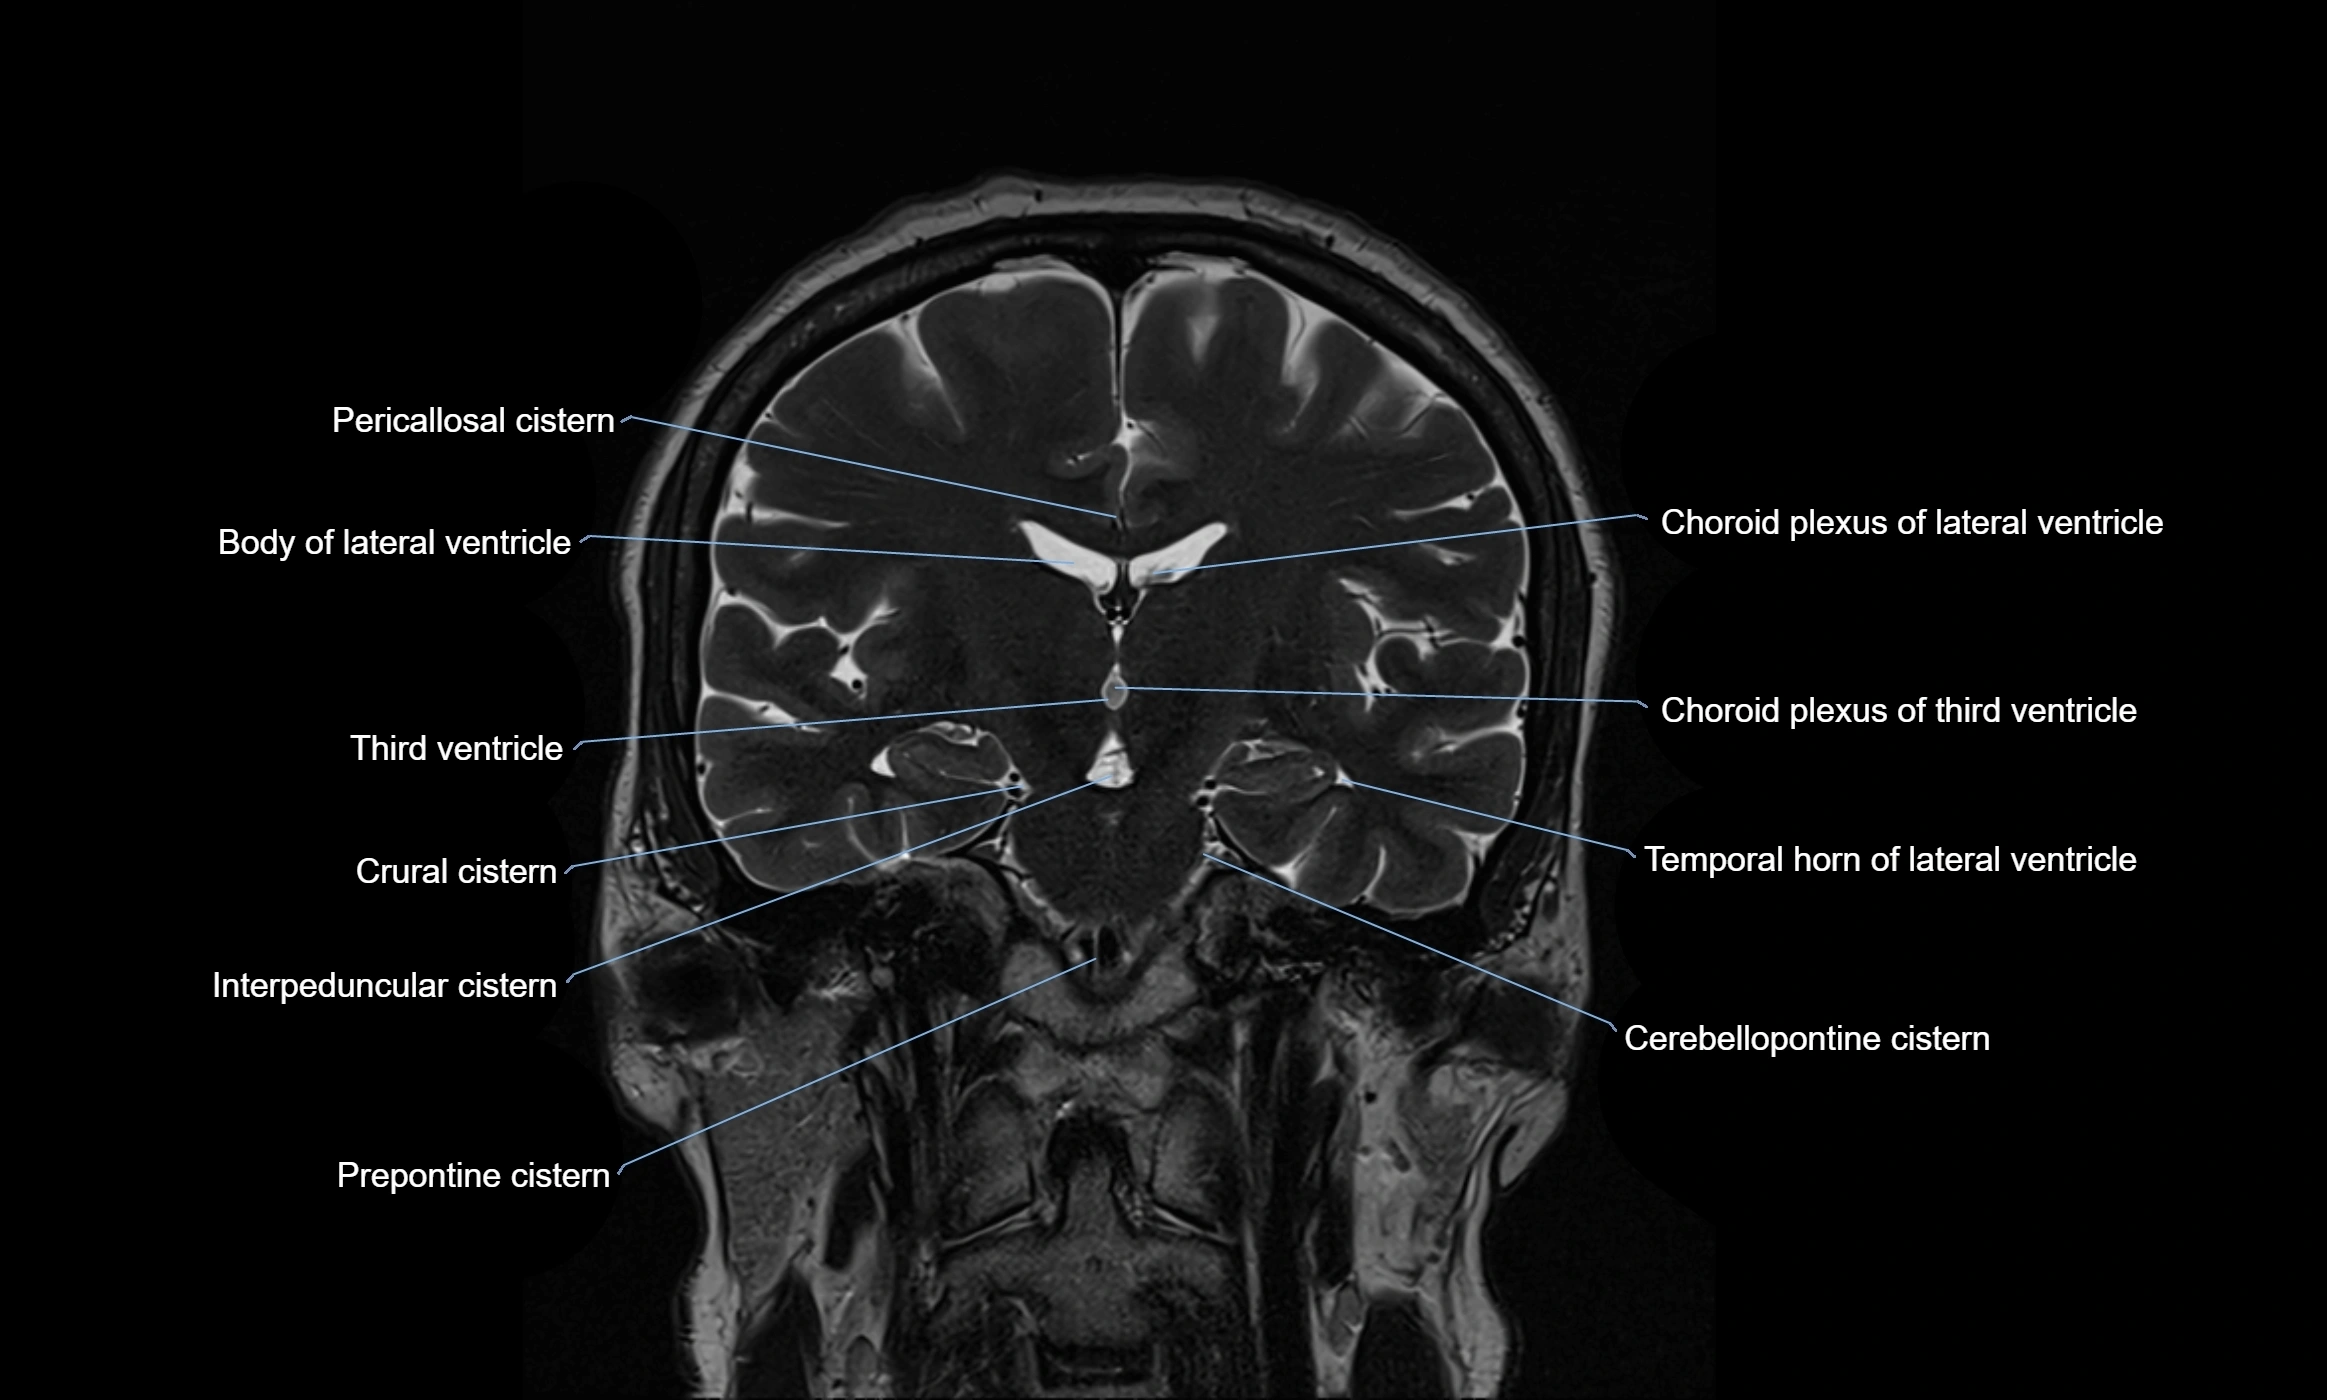

CT image

image